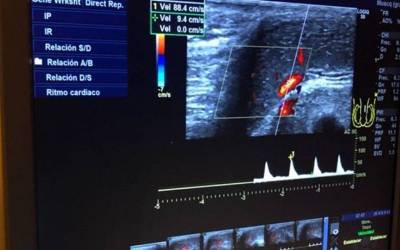

Normalmente, el paciente se coloca tumbado hacia arriba durante la realización de esta prueba. Su duración aproximada es de una hora, ya que se llevan a cabo una serie de mediciones de los cambios vasculares que se originan en el pene, tanto en estado de flacidez como en erección.

Para explorar la erección del pene, nuestro doctor nos explica que "esta erección se consigue mediante la inyección indolora de una sustancia llamada prostaglandina, que actúa sin necesidad de estimulación sexual". De esta manera se pueden observar y medir los parámetros vasculares en tiempo real a medida que se produce la erección.

La eco-doppler ayuda a detectar ciertas alteraciones en el flujo sanguíneo que podrían causar una disfunción eréctil de origen vascular, algo que ocurre entre el 30 y el 50% de los casos. En particular, esta prueba facilita el diagnóstico de la insuficiencia arterial, venosa o mixta en el pene. En esta línea, nuestro doctor declara que "esta prueba también es importante en los pacientes con disfunción eréctil psicológica, puesto que ayuda a demostrar la ausencia de causas orgánicas en los problemas de erección".

En cuanto a su realización, nuestro urólogo nos explica que "la ecografía del pene para la evaluación de la disfunción eréctil se realiza con el paciente en posición supina y con la ayuda de medicamentos erectogénicos inyectados directamente en los cuerpos cavernosos".